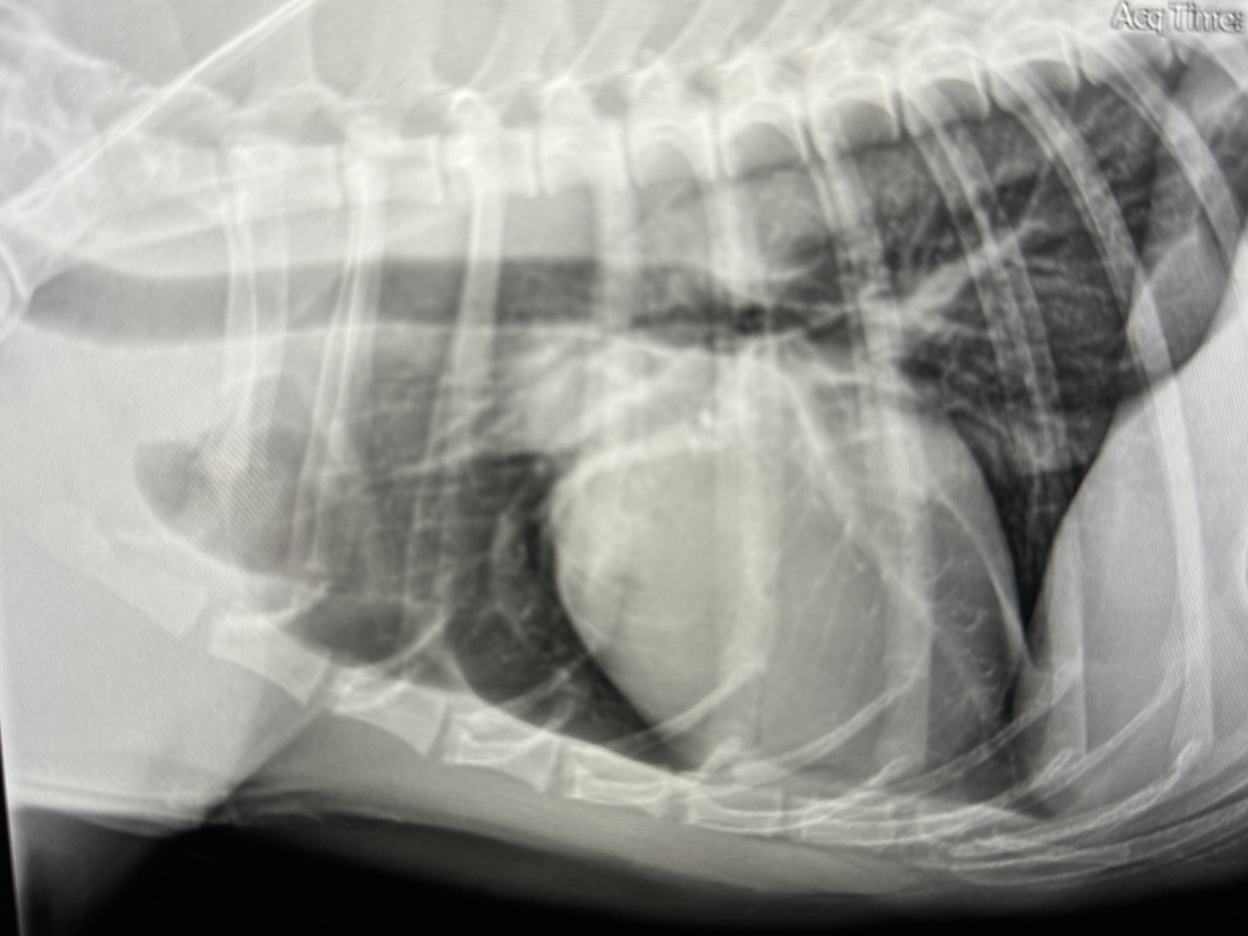

Learn to identify presenting signs and symptoms of heart failure, pericardial effusion, ATE, and caval syndrome.

Join us in this course where you will gain the expertise to triage and stabilize cardiac emergencies in veterinary patients. Led by renowned expert Dr. Rebecca Saunders, DVM, DACVIM (Cardiology), you will learn immediate treatment protocols, identification of cardiac conditions, and essential stabilization techniques to enhance patient care. Take the first step in mastering cardiac emergencies today.